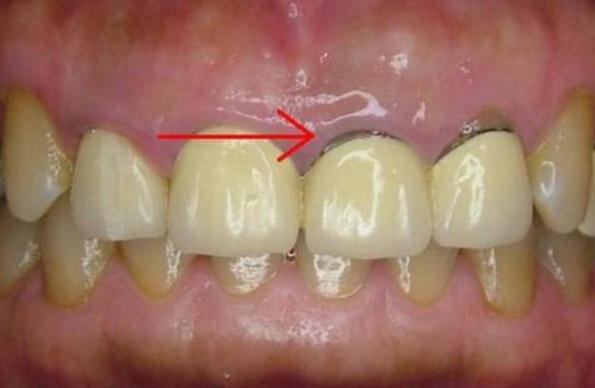

烤瓷修复牙冠边缘与牙龈密合程度是判断烤瓷牙是否成功最重要的指标,密合不佳则会使细菌进行牙冠内,导致牙齿发言、牙龈萎缩、牙龈发黑等。

4、冠体材料更换